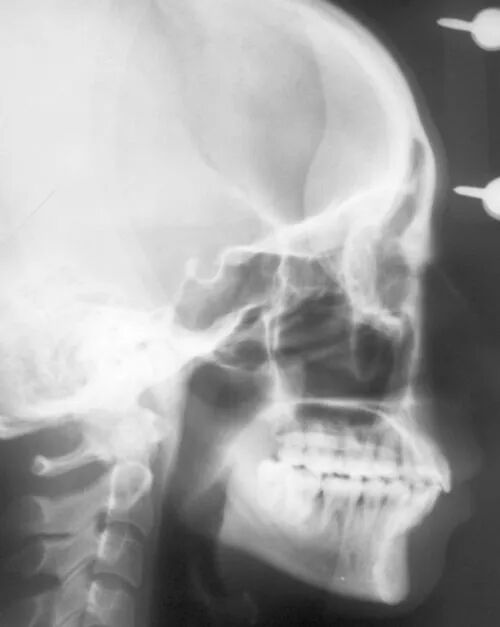

侧方位展现牙骨位置,通常拍摄曲面断层片的机器也可以拍摄头颅侧位片。

这种牙片在正畸邻域应用最为广泛,诸如正畸(牙齿矫正)前的数据分析,制定矫正计划等,头颅侧位片则是重要参考依据。